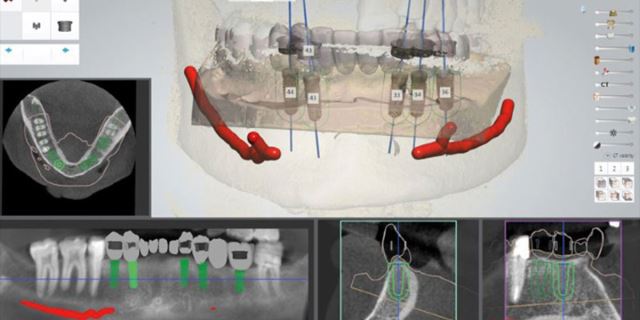

درمان ایمپلنت یک روزه به روش کاملا دیجیتال

برای کاشت ایمپلنت فوری یا ایمپلنت یک روزه، نیازی نیست ابتدا مراحل چند ماهه جوش خوردن ایمپلنت به استخوان را پشت سر بگذارید و پس از آن روکش بر روی دندان تان نصب شود، بلکه در همان روزی که ایمپلنت در دهانتان قرار می گیرد روکش دندان هم بر روی آن نصب می شود. در درمان ایمپلنت به صورت دیجیتال به منظور بررسی استخوان فک و همچنین موقعیت قرار گرفتن رشته های عصبی، از مدل سازی کامپیوتر سه بعدی استفاده می شود. با این شرایط متخصص دندانپزشک با کمترین شکافی به کاشت ایمپلنت دندان می پردازد. به دلیل شکاف کمتر در این روش، درد کمتری برای بیمار وجود خواهد داشت. همچنین به دلیل قرار گرفتن اطلاعاتی بسیار دقیق در دست متخصص دندانپزشک، کمترین میزان آسیب و خطا در این نوع روش درمانی دیجیتال وجود دارد. در کاشت ایمپلنت دیجیتال برای جلوگیری از آسیب عصب و دندان های کناری، یک هدایت کننده (گاید جراحی) بر روی دندان ها نصب می شود. که همین راهنما به برش های دقیق و کوچک تر متخصص دندانپزشک کمک می کند.

مرحله دوم

برای ضبط دقیق تر آناتومی استخوان و دندان ها، در مرحله ی دوم یک سی تی اسکن پرتو مخروطی انجام می گیرد. در این سی تی اسکن، ساختاری سه بعدی از استخوان، سینوس ها و اعصاب به دست می آید. در ادامه تصاویر مرحله یک و دو با یکدیگر ترکیب شده و از دندان ها و استخوان دهان بیمار، مدلی سه بعدی ایجاد می شود.

در این مرحله پس از بررسی های لازمه قطر و طول ایمپلنت انتخاب می شود. پس از اینکه متخصص دندانپزشک طرح مورد نظر را تصویب کرد، مرحله بعدی انجام می گیرد.

مرحله چهارم

در این مرحله به کمک CAD-CAM یک گاید به صورت قالب پلاستیکی ساخته می شود. این مرحله برای قرار دادن ایمپلنت نهایی بسیار کمک دهنده می باشد. گاید تهیه شده در دهان بیمار قرار داده می شود تا بدون برش ایمپلنت درون جایگاه مورد نظر قرار بگیرد.

در روش ایمپلنت دندان معمولی، متخصص دندانپزشک برای مشخص کردن محل کاشت، لثه را تا استخوان به شکل عمودی برش می دهد، در حالی که در ایمپلنت دیجیتال این برش به کمک عکس های سی تی اسکن سه بعدی و گاید جراحی انجام می شود که به همین جهت برش ایجاد شده به میزانی کوچک است که به بخیه زدن نیز نیازی ندارد. کاشت ایمپلنت دیجیتال، با کوتاه کردن زمان بهبود، امکان خونریزی و عفونت را نیز کمتر می کند و به طور کلی زمان جراحی 15 الی 30 دقیقه می باشد. به همین دلایل درد بسیار کمتری نسبت به روش معمولی کاشت ایمپلنت دندان دارد.